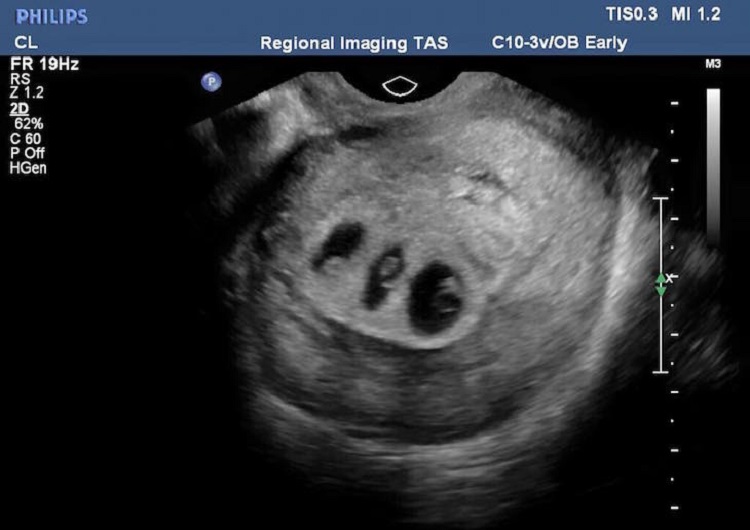

Un día, durante la ecografía de rutina, el médico notó algo increíble. «Veo a un bebé aquí y otro más arriba», – dijo con calma el ginecólogo. «¿Quiere decir que traigo gemelos?» – preguntó incrédula Chloe. Segundos después, el médico movió la sonda de ultrasonido y se fijó en un pequeño espacio entre los dos fetos. «Bueno, y aquí está el tercero», – dijo con entusiasmo el médico.

¡El útero de la mujer albergaba a tres nuevos frutos! Según los expertos, esto sólo es posible una vez cada varios cientos de miles de embarazos.